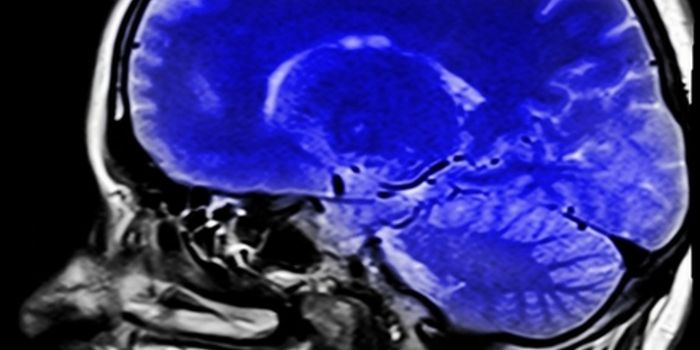

APR 14, 2015CancerAn experimental drug that attacks brain tumor tissue by crippling the cells' energy source called the mitochondria has p ...

AUG 11, 2016CancerIn 2014 the most common cancer diagnosis was breast cancer, followed by prostate, lung, colon, skin, and brain cancer. B ...